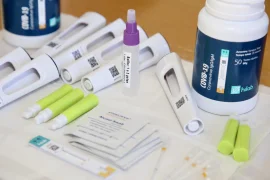

Pesquisadores desenvolvem Teste Popular de COVID-19 que amplia acesso ao diagnóstico

4ª ação ampliada de diagnóstico da COVID-19 aplica mais de mil testes em Bauru

Ação de diagnóstico da Covid-19 aplicará testes a carros e motos em geral neste sábado (08)

Secretaria de Saúde faz nova ação de testagem para Covid-19 neste sábado (08)

Prefeitura realiza ação ampliada de diagnóstico para a Covid-19 neste sábado (25)

Ação de testagem para Covid-19 detecta 145 casos positivos neste sábado em Bauru

Bauru realiza 1.200 testes para Covid-19 neste sábado (11)

Startup ajuda a baratear teste molecular de COVID-19

Prefeitura de Bauru doa testes rápidos de Covid-19 para Hospital Estadual

Desenvolve SP investe na produção de teste que detecta coronavírus

Startup busca desenvolver teste totalmente nacional para Covid-19